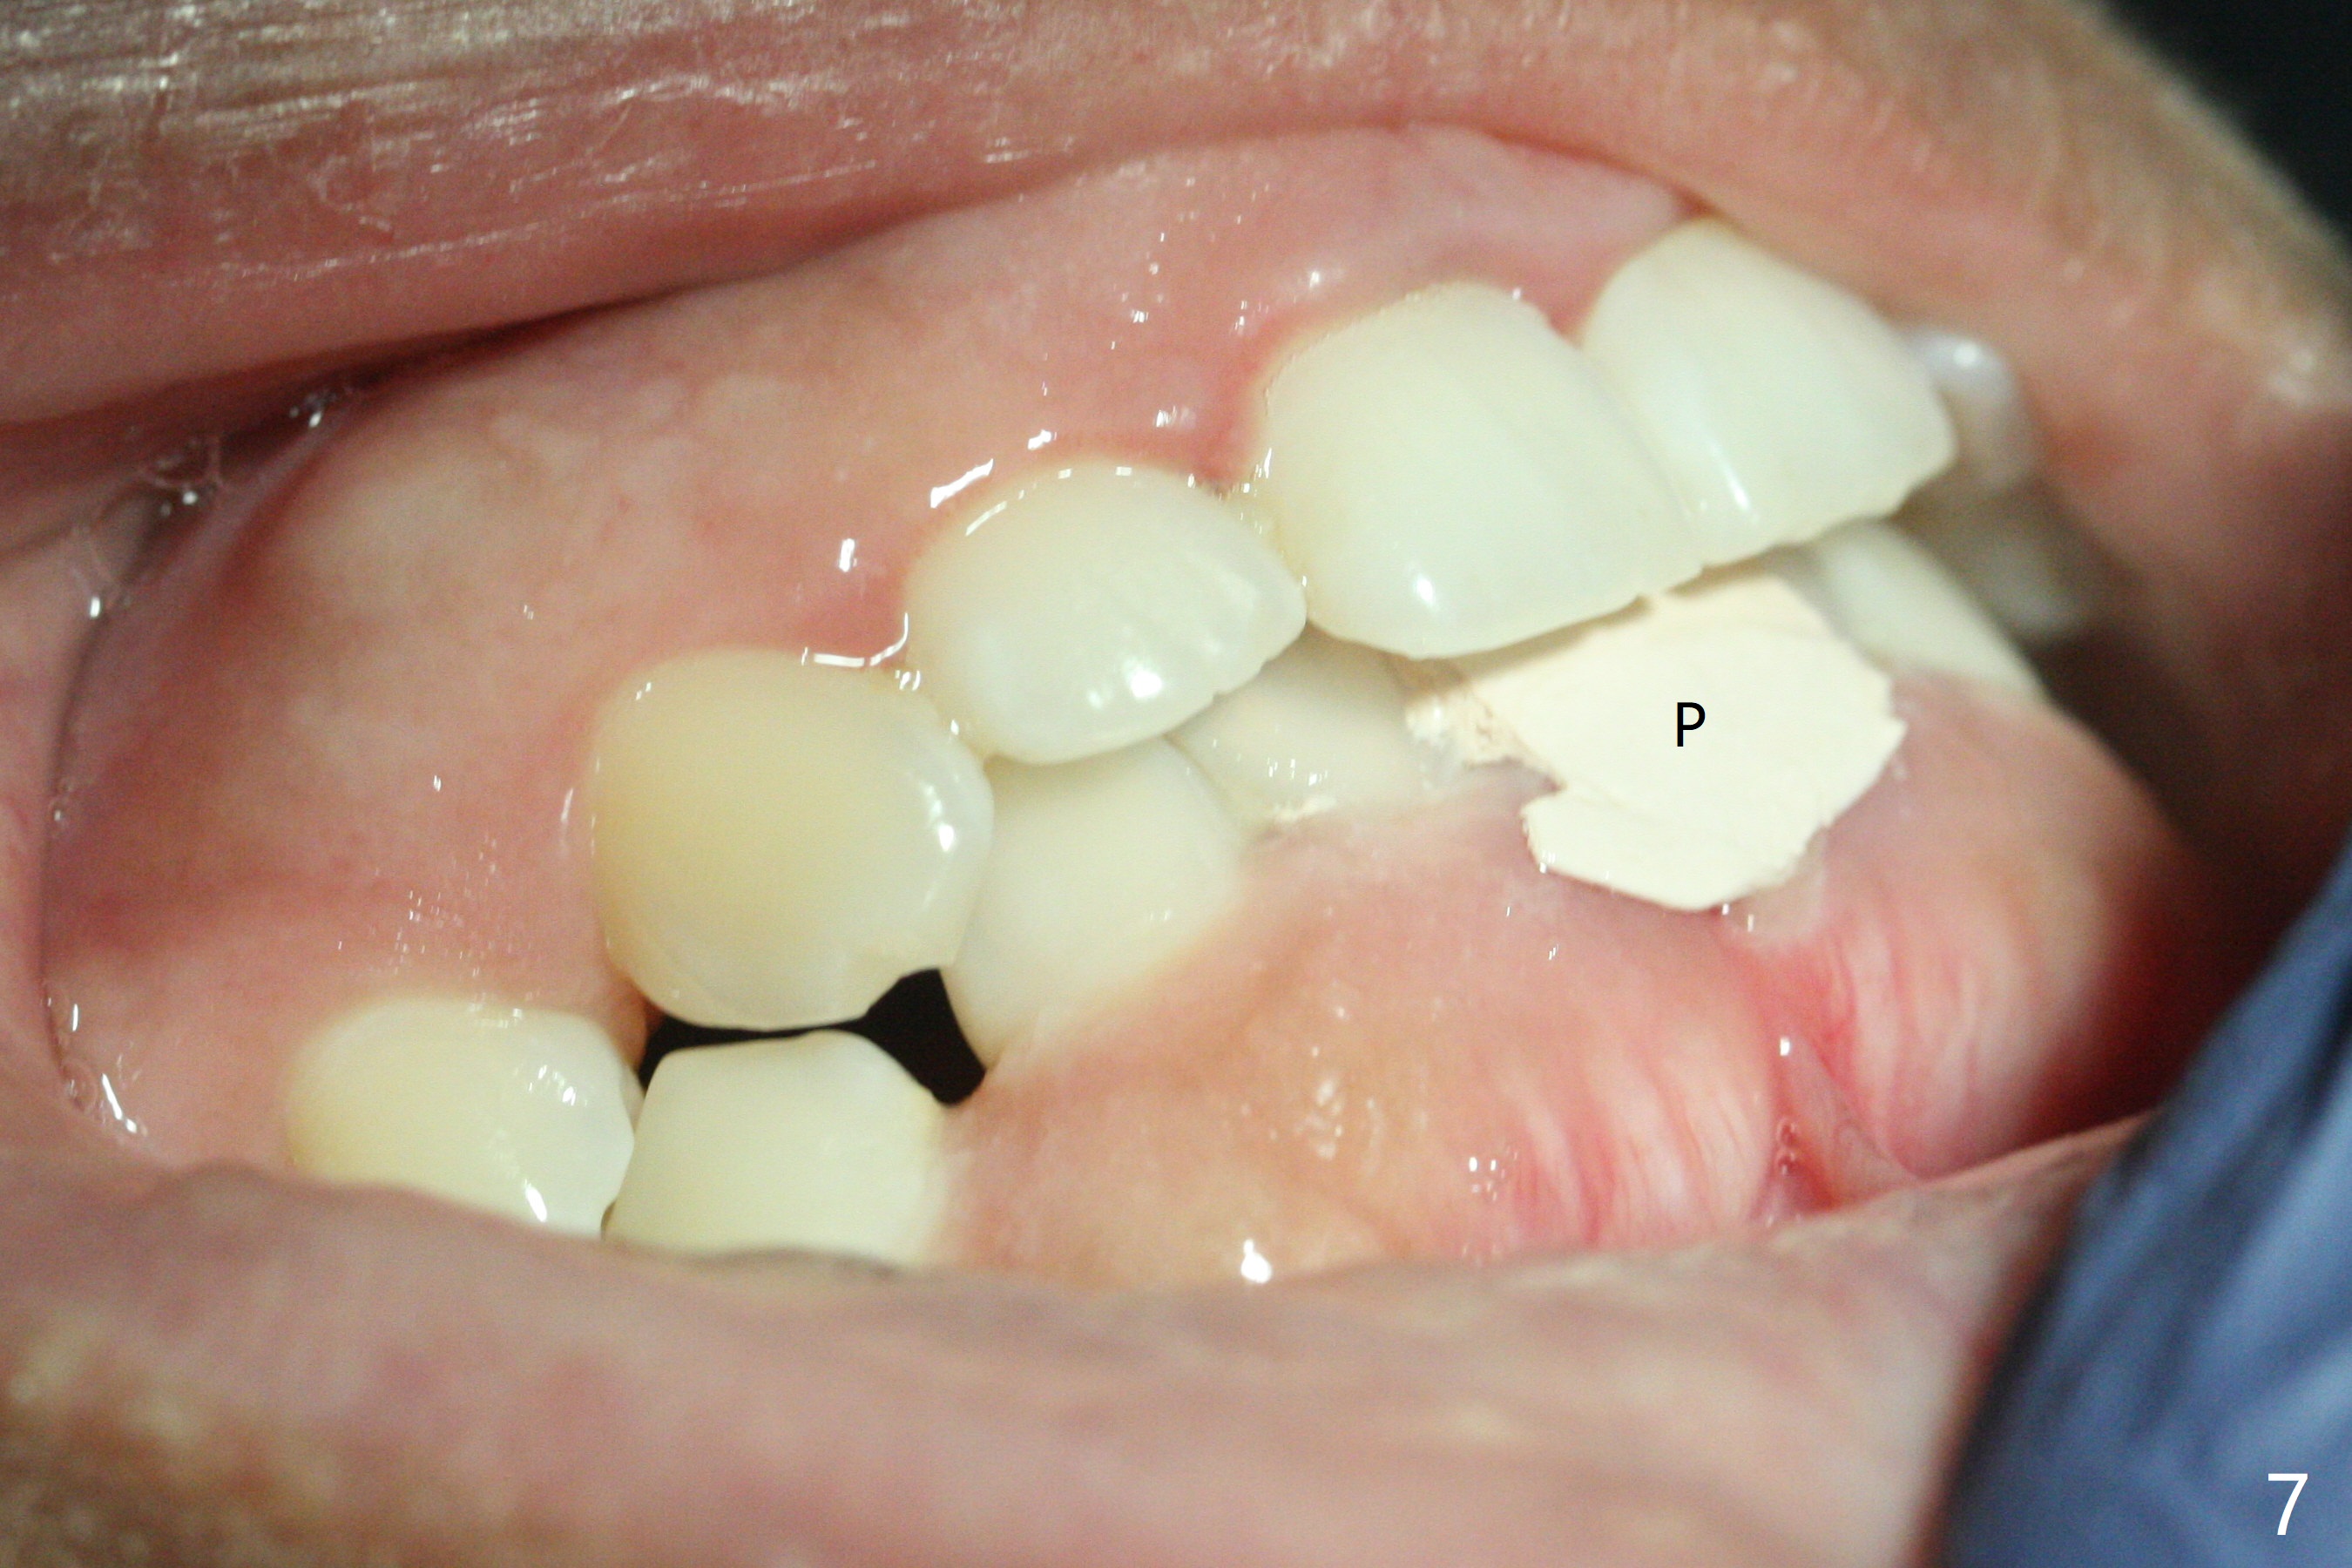

A 31-year-old woman fractured the lower left central incisor when it was hit by her 2-year-old son's head with mesiobuccal subgingival margin (Fig.1). After RCT (Fig.2), gingivectomy is conducted with eletrosurg to expose the fractured margin (Fig.3). In 2 days, a prefabricated fiber post will be bonded with the tooth and the fractured fragment together. To extend the use of the incisor, two implants are required (Fig.4). As scheduled, the patient returns with the fractured portion (Fig.5,6 (buccal (B) and lingual (L) views)). The periodontal dressing is in place (Fig.7 P). After preparation of the post space, the fiber post (Fig.10 (P)) is bonded with resin cement (Fig. 10 ^ and *) to the tooth and fragment with rubber dam (Fig.8). The patient is pleased post occlusal adjustment (Fig.9).